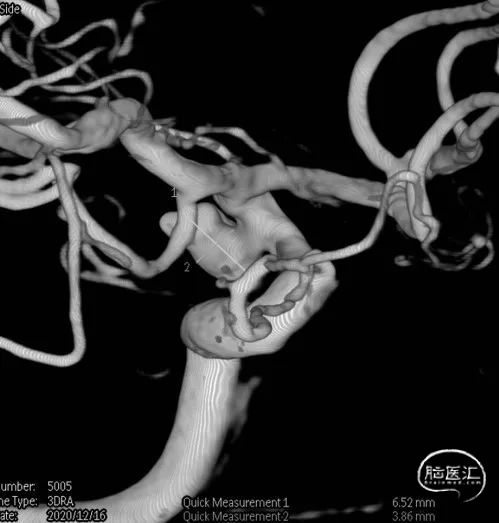

图1

术前DSA影像